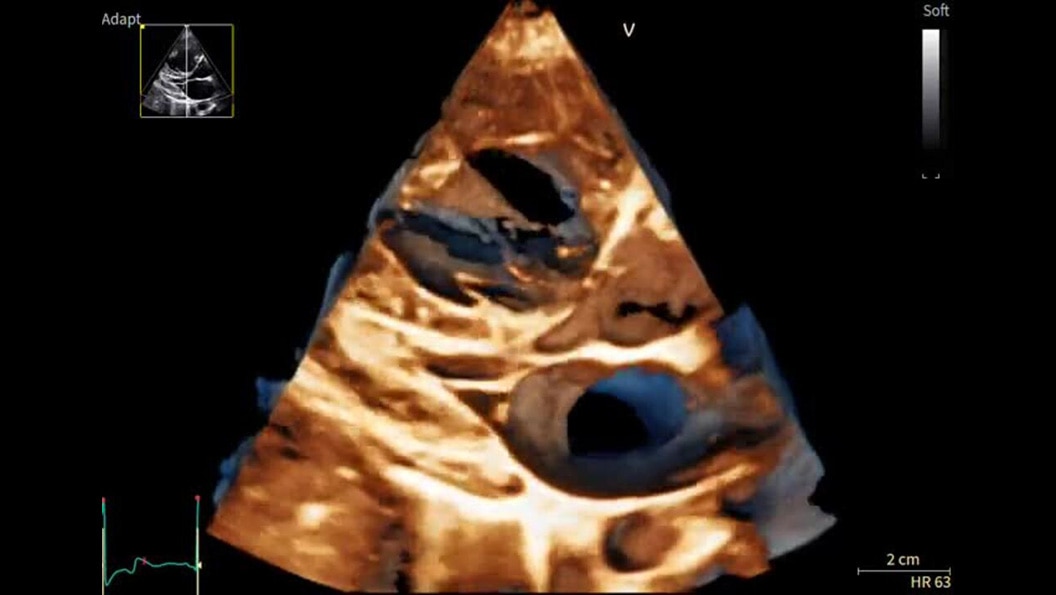

Sharp images, instant clarity

Discover extraordinary image clarity and precision

Designed to take you further, next-generation cSound Pioneer works in harmony with our sophisticated probe technology to deliver enhanced detail, a new level of Color Flow, and incredible 4D imaging for clinical confidence from the first scan.